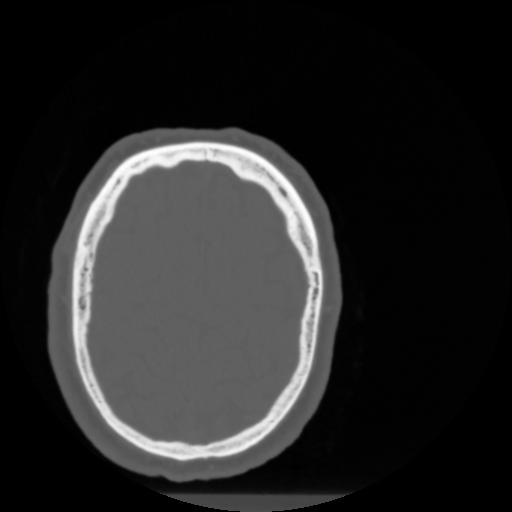

4 CEREBRO,,Vol,0.5,CEREBRO,,